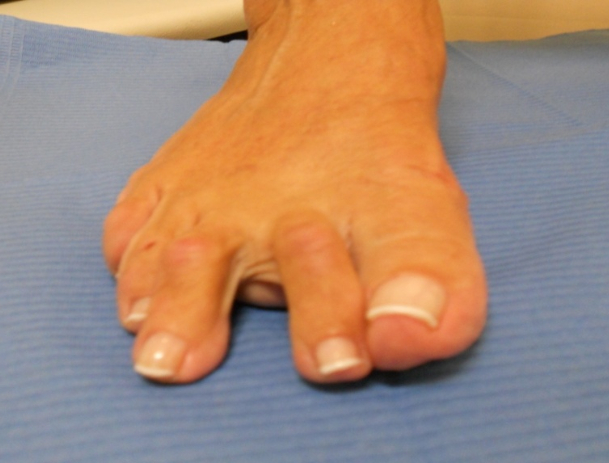

Hallux Valgus (juanete)

Hallux valgus: antes Hallux valgus: después